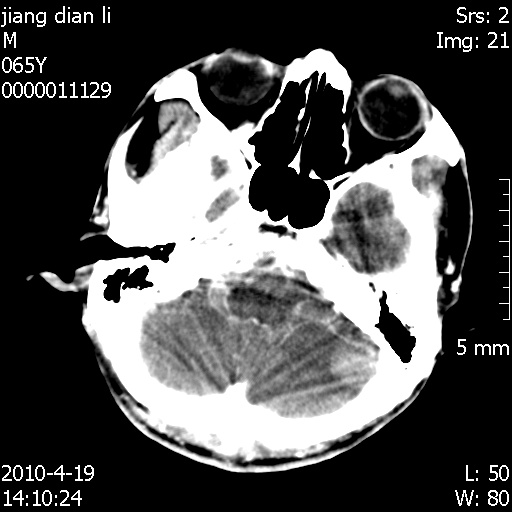

老年男性,突发左下肢无力1天,其余有价值的检查都没有。平扫ct值大约60hu,增强后ct值没什么改变,请大家讨论一下这个病例是什么?说明诊断理由。

左小脑、右大脑顶叶多发圆形高密度病灶,其周环状低密度影。考虑多发脑出血。隔期观察。

今天上班后发现病人前天复查(4月18日发病,19日初诊,22日复查),三个病灶均明显增大,边缘仍旧清楚,水肿加重,右侧脑室基本闭塞。

我想:如果是肿瘤出血的话,一般不会导致体积明显改变,水肿又进一步加重;如果是出血灶,那么现在应该正好是水肿加重的时候,还是比较符合,但是为什么边缘又是这样的特点?